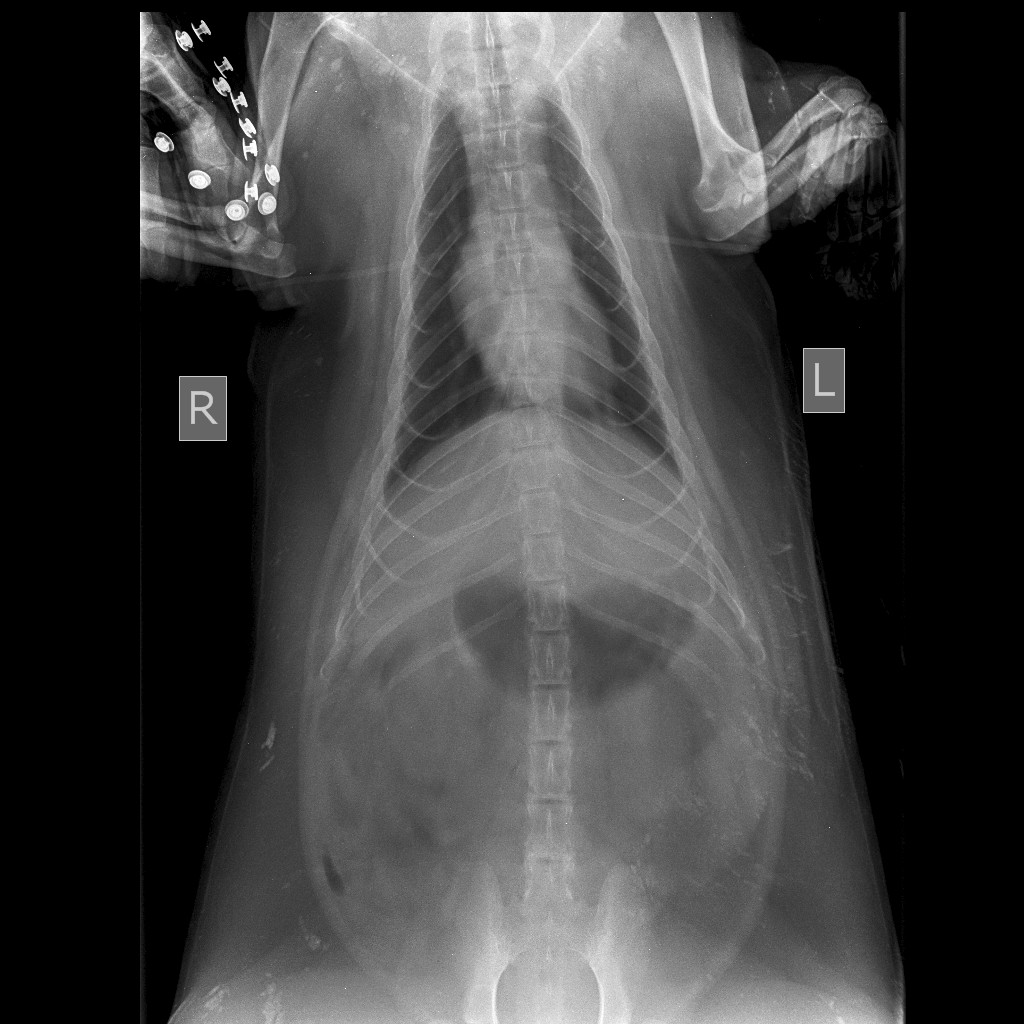

Как рассказали в клинике, барсуку обезболили, сделали УЗИ брюшной полости, обработали от блох и клещей, провели рентгенобследование позвоночника, сделали анализы крови, в том числе на бабезиоз и дали заключение — у барсука обезвоживание, анемия и поражение грудо-поясничного отдела позвоночника неясного генеза, поскольку явных переломов позвоночника по снимкам не выявлено. Причины, по которым зверек пока не пользуется задними лапами, или дифференциальных диагнозов два:

- перелом позвоночника, который не всегда виден на рентгене;

посттравматический спинальный шок.

Для того чтобы определить истинную причину, необходимо сделать МРТ-исследование позвоночника, которое планируют провести сегодня. Сейчас барсуку в клинике проводится дегидратационная терапия, обезболивание и симптоматическая терапия.